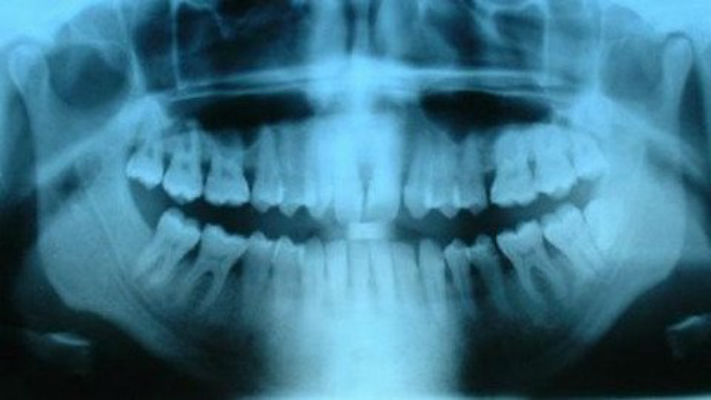

L’Organizzazione mondiale della Sanità ricorda come le otturazioni siano la causa maggiore di assunzione di mercurio nella popolazione. In bocca transitano bibite gassate, acidi alimentari, sali e liquidi alcolici che causano un continuo rilascio in basse dosi di mercurio.

Stop al mercurio nei denti. Anche gli alimenti assunti ad alte temperature causano il rilascio di vapori di mercurio, come dimostra il video più sotto. Alla tossicità del mercurio sono correlati numerosi sintomi, tra cui la depressione, l’emicrania, la perdita di memoria, le gengiviti, l’Alzheimer, il Parkinson, l’autismo, la stanchezza cronica. Per questo motivo alcune nazioni come la Danimarca, la Finlandia e la Svezia da tempo hanno abolito l’uso dell’amalgama.

Il Dr. David Kennedy, dell’Accademia Internazionale di Medicina Orale e Tossicologia già da tempo ha dimostrato che a 37°C le otturazioni emettono un vapore a base di mercurio altamente tossico.